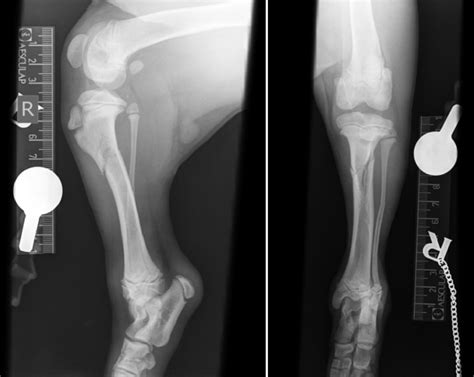

Diagnosis of Tibial and Fibular Fractures

Diagnosing tibial and fibular fractures typically involves a combination of physical examination and imaging tests. The diagnostic process may include:

• X-Rays: Standard X-rays to visualize the bones and determine the location and severity of the fracture.

• CT Scans: For more detailed images, especially in complex fractures.